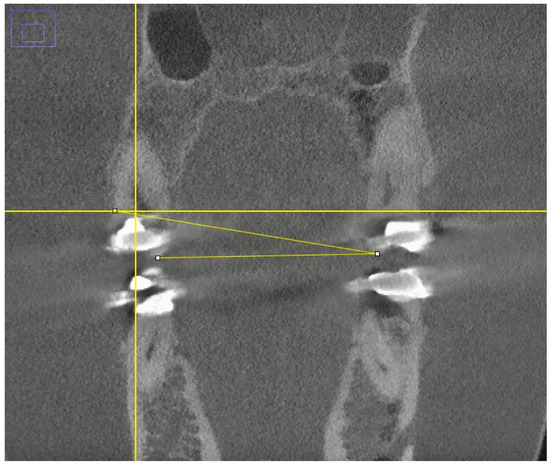

Head Tilt as a Technique to Reduce Contralateral Arch Artifacts in Small Field of View Cone Beam Computed Tomography Imaging

by Dominik Niklas Elvers, Marius Meier, Dritan Turhani, Sebastian Fitzek, Philipp Johann Poxleitner and Jörg Philipp Tchorz

Oral 2026, 6(2), 29; https://doi.org/10.3390/oral6020029 - 9 Mar 2026

Background/Objectives: Cone beam computed tomography (CBCT) is vital in endodontics but suffers from beam-hardening artifacts caused by metallic restorations, which can obscure diagnostic details. This study evaluated a novel patient positioning protocol—a controlled head tilt—designed to mitigate these artifacts by moving contralateral metallic [...] Read more.

Background/Objectives: Cone beam computed tomography (CBCT) is vital in endodontics but suffers from beam-hardening artifacts caused by metallic restorations, which can obscure diagnostic details. This study evaluated a novel patient positioning protocol—a controlled head tilt—designed to mitigate these artifacts by moving contralateral metallic structures outside the primary X-ray path in small field of view (FoV) CBCTs. Methods: Using a skull phantom with metallic restorations CBCT scans were acquired in three positions: standard alignment, a 12° tilt toward the region of interest (ROI), and a 12° tilt to the opposite side. Fifty experienced dentists, blinded to the protocol, subjectively compared image quality and artifact severity between the tilted and reference images. Results: The tilt away from the ROI was rated as providing better image quality significantly more often than the tilt towards the side of the ROI (442 of 585 non-tied comparisons; p < 0.001). A complementary rater-clustered GEE analysis adjusted for slide confirmed higher odds of “better” ratings under head tilt away from the ROI for image quality (OR = 4.16, 95% CI 3.12–5.56) and artefacts (OR = 2.87, 95% CI 1.93–4.26). An individual head tilt significantly improves subjective small-FoV CBCT image quality, most evidently in the longitudinal plane, by reducing artifact interference from contralateral metals, and should be considered a practical strategy for clinical use, and may serve as a practical chairside strategy, pending clinical validation. Full article